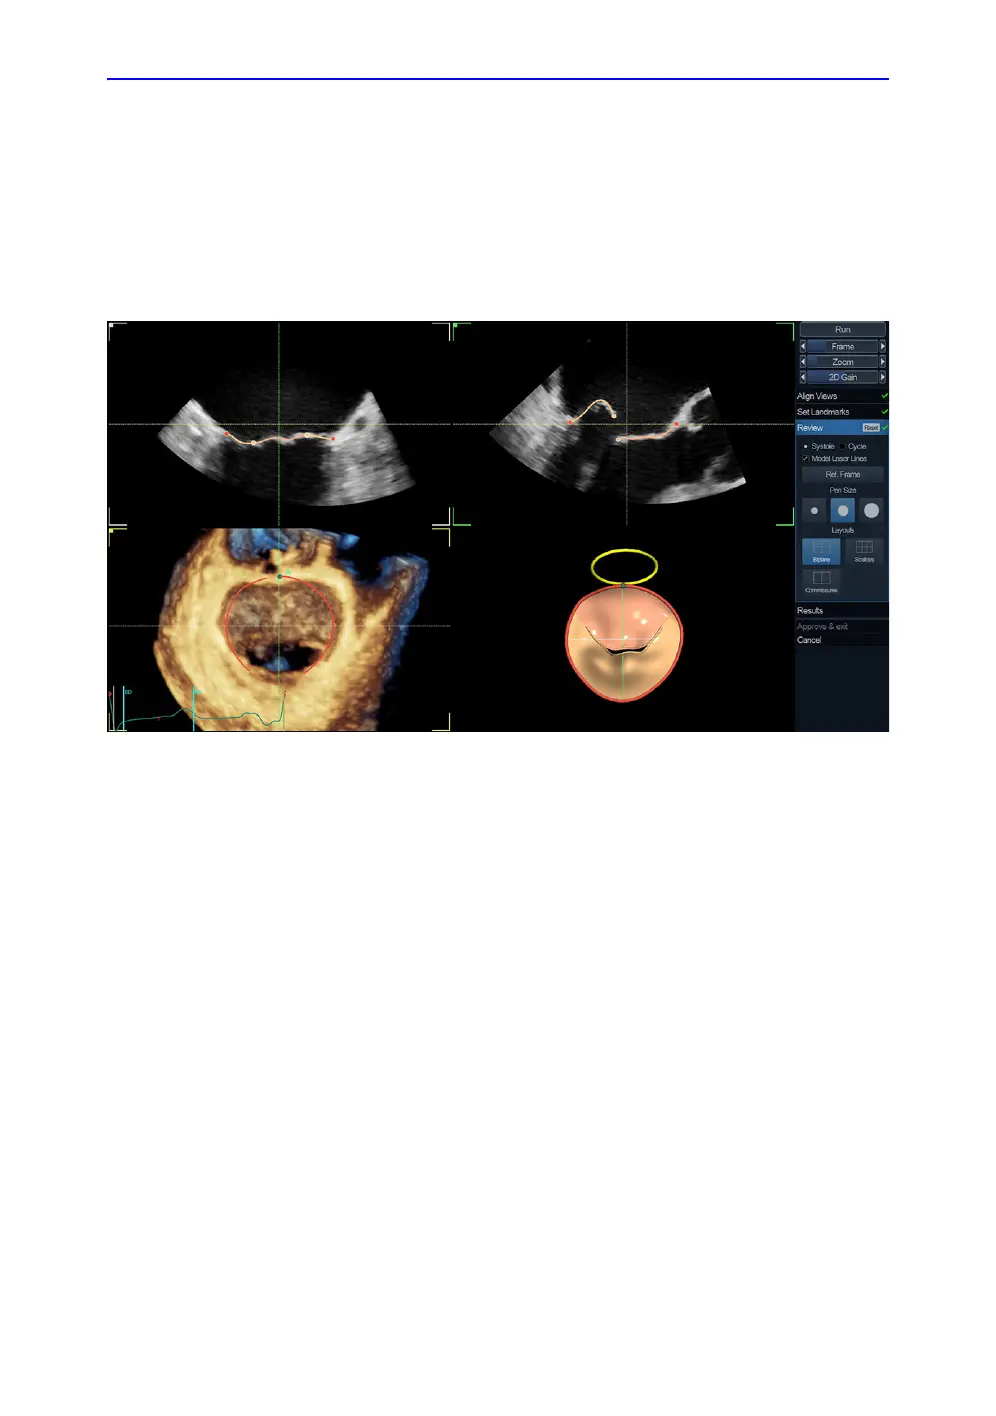

1. The Review stage is automatically entered.

The default screen displays two long axis views (MC and

APLAX), short axis 3D view at the annulus plane aligned

according to surgical view (the 3D looking from atrium to MV

and with aortic valve on top) and an interactive 3D view of

segmented MV (Figure 8-38).

Figure 8-38. The Review stage

2. The MV segmentation should be checked in all slices. To

visualize the MV segmentation in all slices, rotate the

reference slices in short axis view (dotted lines) and observe

the segmentation in the interactive view. In 3D interactive

view the model laser lines update according to slice position

in the 3D short axis view. The segmentation is correct when

segmented model overlaps MV leaflets.